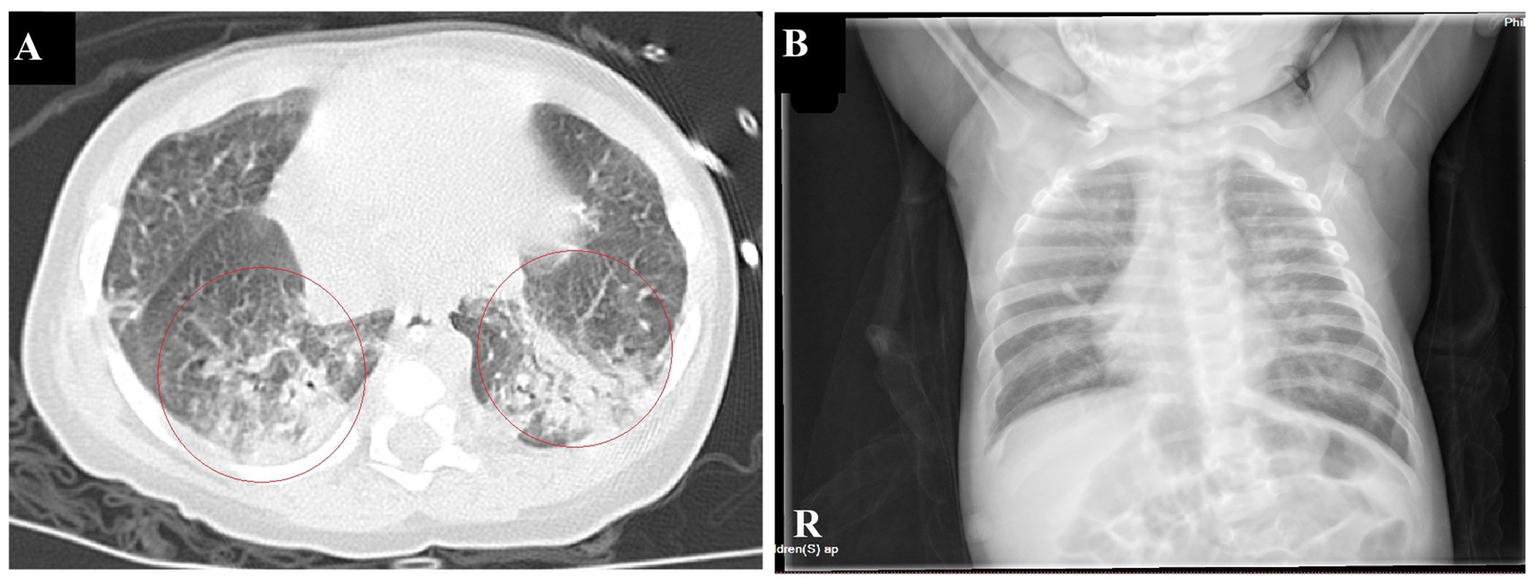

The infant had coinfections with B. pertussis, RSV, and CMV, with B. pertussis invading the bloodstream. The infant’s vital signs are stable and the degree of infection has improved significantly; therefore, linezolid was discontinued, and azithromycin and meropenem were continued. A repeat blood test indicated a hemoglobin level of 63 g/L, and 1.0 U of red blood cell suspension leukocytes-reduced was administered via infusion. On January 16th, the patient showed notable clinical improvement. Routine blood examination revealed a white blood cell count of 19.54 × 109/L and CRP levels of 10.85 mg/L. Meropenem was discontinued, and the patient was switched to cefoperazone sulbactam (50 mg/kg, Q8H). By January 21st, the patient’s breathing and heart rate had stabilized. A repeat blood test showed a white blood cell count of 15.82 × 109/L (with lymphocytes accounting for 0.571), platelet count of 431 × 109/L, hemoglobin of 73 g/L, and CRP of 3.68 ng/mL. Additionally, 1.0 U of red blood cell suspension leukocytes-reduced was given by infusion. The patient was extubated and switched to high-flow oxygen therapy. On January 23rd, sputum and wet rales in both lungs significantly improved. A repeat blood test showed a white blood cell count of 11.06 × 109/L, with lymphocytes accounting for 0.674, platelet count of 435 × 109/L, and CRP at 2.99 ng/mL. Chest computed tomography indicated significant improvement in inflammation in both lungs (Figure 3A). Cefoperazone-sulbactam was discontinued and replaced with cefozoxime to prevent infection.

Figure 3

Chest imaging before discharge (A). Chest CT on January 23rd shows a significant reduction in patchy hyperdense shadows in both lungs compared to the previous imaging (B). Chest radiographs on February 9th indicate a significant improvement in lung inflammation.

On January 27th, the infant’s general condition was good, with only a few sputum sounds heard in both lungs. The patient was switched to nasal catheter oxygen inhalation therapy. On January 30th, oxygen therapy was discontinued. Repeat blood tests showed a white blood cell count of 8.97 × 109/L, lymphocytes accounting for 0.710, hemoglobin of 90 g/L, and CRP of 2.98 ng/mL, with the current treatment regimen continued. On February 10th, the patient experienced notable relief from clinical symptoms. Laboratory indicators returned to normal, and chest imaging showed substantial resolution of lung inflammation compared to previous examinations (Figure 3B). Based on these positive findings, the patient was discharged from hospital. The child’s guardian was satisfied with the doctor’s attitude and the treatment process. The dynamic results of the laboratory tests of the infants are presented in Table 2 and Figure 4. The critical treatment schedule for infants is shown in Figure 5.